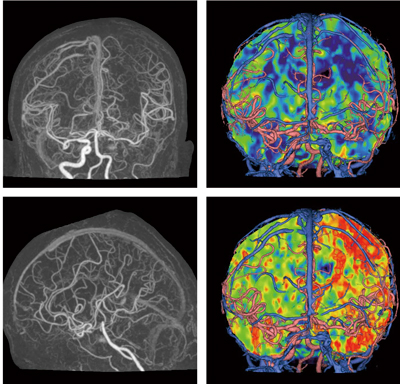

低線量撮影が可能なAIDR 3Dは,160mmの範囲を連続的に撮影できるArea Detector CT「Aquilion ONE」において大きな威力を発揮する。Area Detector CTは,連続的なスキャンにより形態のみならず機能,動態,血流をとらえることが可能である。しかしながら,連続的な撮影は,被ばく増加につながる。AIDR 3Dにより,1 phaseあたりの撮影線量が低減することで,連続撮影を行った場合でも,通常検査と同程度の被ばくに抑えることが期待できる(図3)。

図3 頭部perfusion CT画像(AIDR 3D 使用症例)

80kV,70mAs,1s/rot,0.5mm×320,DyVS Intermittent=17scans

80kV,30mAs,1s/rot,0.5mm×320,DyVS Intermittent=6scans

AIDR 3D Standard

CTDIvol=99.58mGy

DLP=1593.2mGy.cm 3.66mSv(k=0.0023)

(データご提供:藤田保健衛生大学病院様)